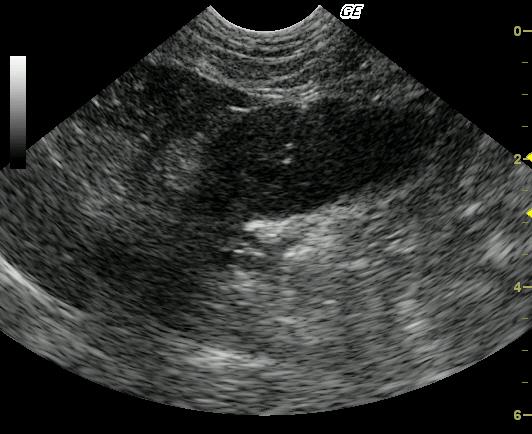

This 8-year-old MN DSH was presented for progressive vomiting and anorexia. The physical exam revealed a palpable cranial abdominal mass, poor body condition, and mild dehydration. CBC presented a mild regenerative anemia while the blood chemistry analysis was normal.